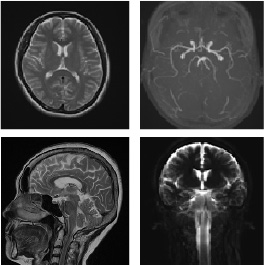

MRI 装置の撮影画像

頭の画像